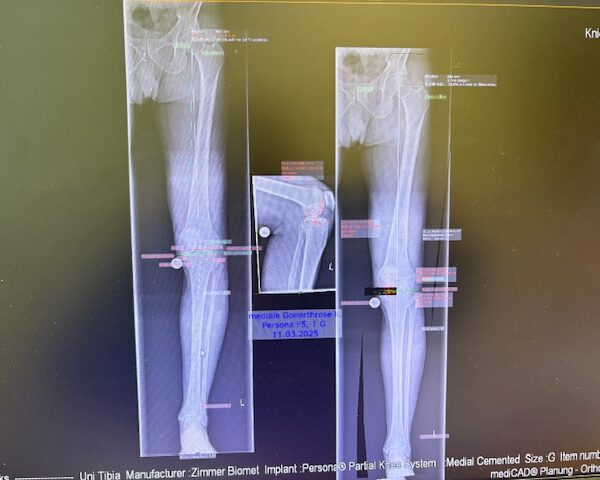

Ο προεγχειρητικός ψηφιακός σχεδιασμός

Πραγματοποιήθηκε απεικόνιση και ψηφιακός σχεδιασμός της επέμβασης, ώστε να προσδιοριστεί με ακρίβεια το μέγεθος και η θέση των προθέσεων. Ο στόχος ήταν να αποκατασταθεί η φυσιολογική μηχανική του γόνατος, διατηρώντας ανέπαφα τα υγιή τμήματα της άρθρωσης, τους συνδέσμους και τους γύρω μυς.